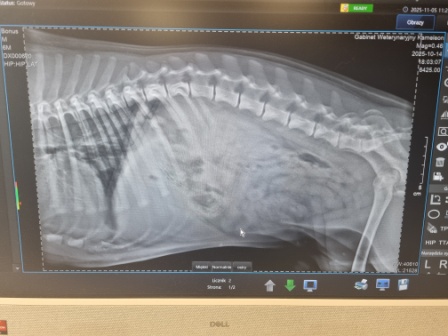

Wiktoria Bagińska, Wiktoria Jastrzębska, Anna Matejczuk i Iza Sosnowska przeprowadziły wywiad z panią doktor, pytając o specyfikę pracy weterynarza, najczęstsze przypadki spotykane w gabinecie oraz o to, jak prawidłowo dbać o zdrowie kotów i psów. Pani Magdalena Kierklewicz przygotowała dla uczennic ciekawe zagadki diagnostyczne – określanie nieprawidłowości na zdjęciach RTG. Było to okazją do poznania, jak duże znaczenie w leczeniu zwierząt mają badania obrazowe.